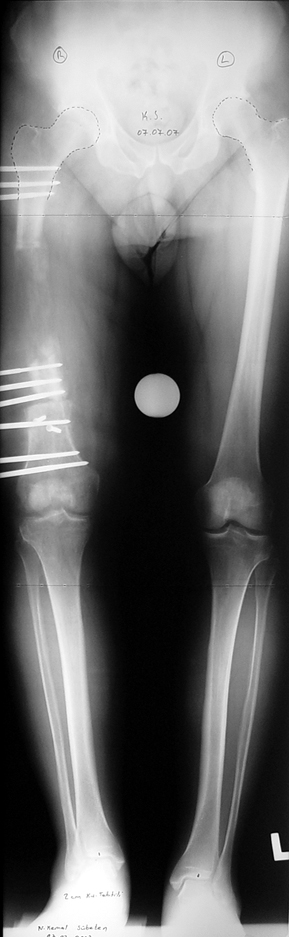

Appropriate radical debridement necessitates excision of all necrotic bone and soft tissues, and frequently causes instability at the involved extremity. The remaining bone and soft tissue defect has to be fixed and reconstructed. The distraction osteogenesis method of Ilizarov is used successfully for achievement of union, correction of the deformity, elimination of limb length inequality and reconstruction of segmental bone defects.

The duration of external fixation (external fixation index) depends on the amount of distraction required, and the extremity is prone to complications during this period. After the distraction phase is completed, the external fixator remains in place during the consolidation phase, which lasts twice as long as the distraction phase; but this period is hardly tolerated. If the external fixator is removed before sufficient consolidation is achieved, fractures, deformity and shortness will be the result. In our department, ‘lenghthening over nail’ method is used in order to decrease the external fixation index and increase patient comfort and activity level. In this method, the intramedullary nail is statically locked after the completion of the distraction phase, and external fixator is removed. The extremity is stabilized by the intramedullary nail during consolidation phase. In this way, complications due to long external fixation index or early removal of the external fixator are avoided.

Case 1